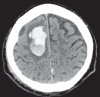

Background: Cerebral amyloid angiopathy (CAA) is a degenerative vasculopathy that is classically associated with lobar intracerebral or sulcal hemorrhage. Its prevalence is estimated at 30% in the seventh decade and 50% in the eighth and ninth decades. In this review, we summarize the risks linked to CAA with respect to the treatment and prevention of stroke.

Results: Among patients given systemic lytic treatment for stroke, those who have microhemorrhages tend to have a higher risk of treatment-associated brain hemorrhage. In a meta-analysis, 70% of patients who sustained a hemorrhage after thrombolytic therapy were found to have CAA, compared to only 22% in a control population. Patients with cerebral hemorrhages have microhemorrhages more commonly than patients with transient ischemic attacks (TIA) or infarcts. This was observed among persons under treatment with vitamin K antagonists (odds ratio, 2.7) or platelet aggregation inhibitors (odds ratio, 1.7). Moreover, the apolipoprotein E2 allele is associated with a higher incidence of intracerebral hemorrhage (ICH) under oral anticoagulation. Strict treatment of arterial hypertension can lower the risk of ICH in persons with probable CAA by 77%. On the other hand, the use of statins after a lobar ICH increases the risk for a clinically manifest recurrent hemorrhage from 14% to 22%.